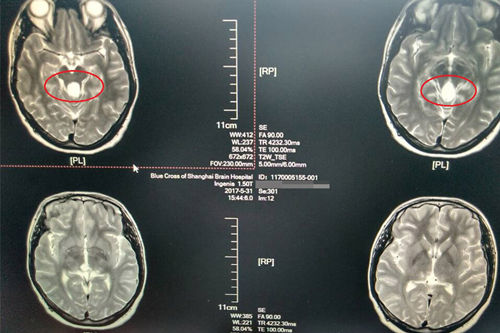

術(shù)前:核磁診斷松果體占位(圖片中央白色區(qū)域)

今年的3月份,李瑩忽然感到雙眼視物模糊,偶爾出現(xiàn)重影的情況,在丈夫的陪同下,李瑩到上海藍十字腦科醫(yī)院進行了全面的檢查。檢查中發(fā)現(xiàn),李瑩中腦四疊體旁有一囊性占位,供血不甚豐富,對四周結(jié)構(gòu)造成壓迫。

在對患者實施手術(shù)之前,我院神經(jīng)外科諸位專家進行了充分的論證,各位醫(yī)生紛紛建言。沈建康、侯增欣等專家參與了患者的病情討論會,大家得出了較為一致的結(jié)論,患者顱內(nèi)松果體區(qū)占位,囊腫增大,有手術(shù)指征,建議擇期行“松果體腫瘤切除術(shù)”。